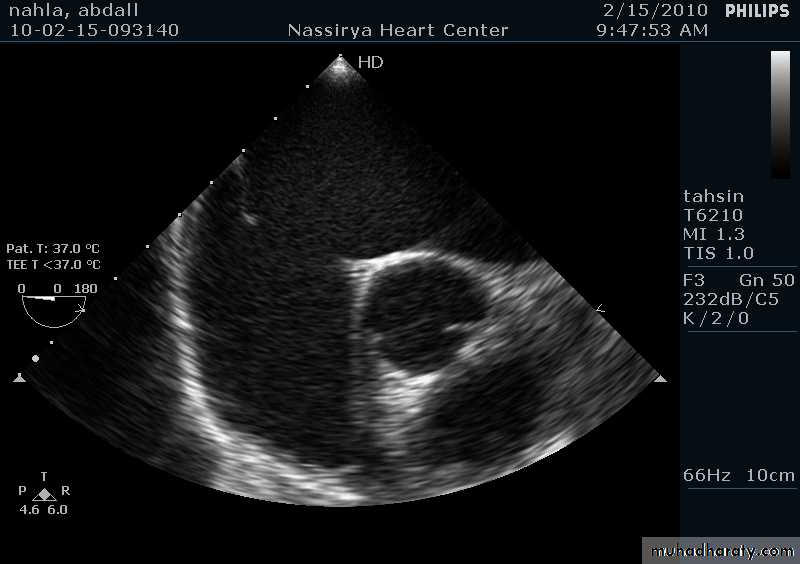

33Echocardiography & TEE

Shows the size of the defectThe direction of blood flow

The pulmonary artery pressure34

Ostium Primum ASD

37

38